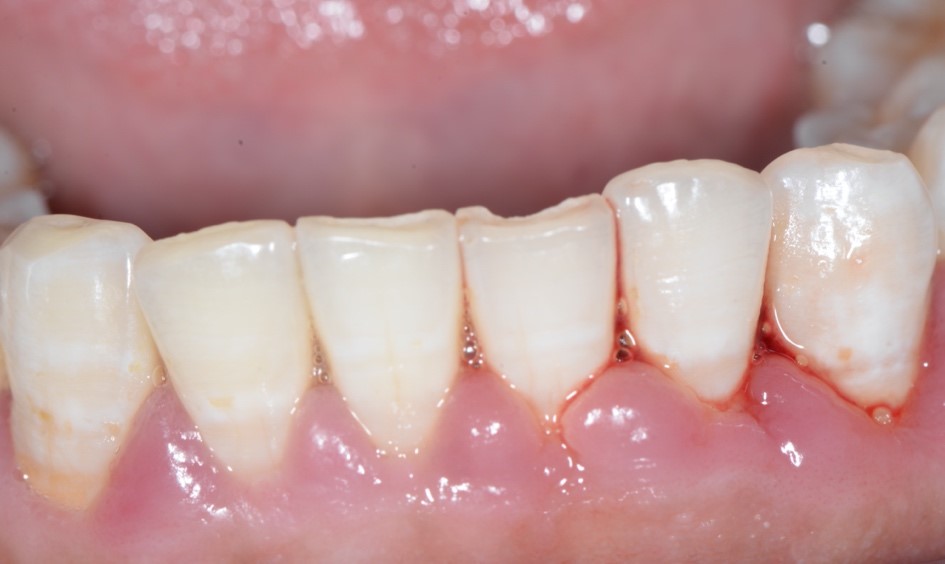

图1:牙龈出血

牙龈出血是口腔常见症状,也是最容易被大众忽视的症状之一。牙龈出血可在许多情况下出现,例如刷牙、使用牙线/牙签/牙间隙刷、吮吸或咀嚼较硬食物时,甚至在没有任何刺激的情况下自发出血。根据2018年出版的《第四次全国口腔健康流行病学调查报告》,35-44岁居民中,牙龈出血检出率为87.4%,但知道“刷牙出血不正常”的人仅占68.7%。